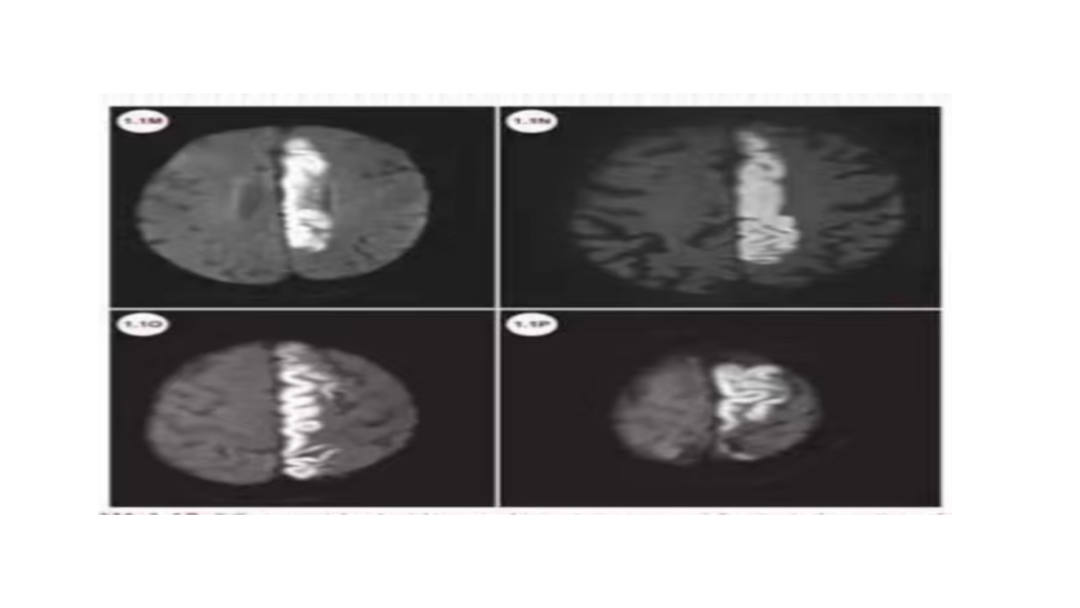

一例左侧大脑中动脉M3段闭塞远端

抽吸导管血管再通治疗

作者:高军、温昌明

视频动图如下: